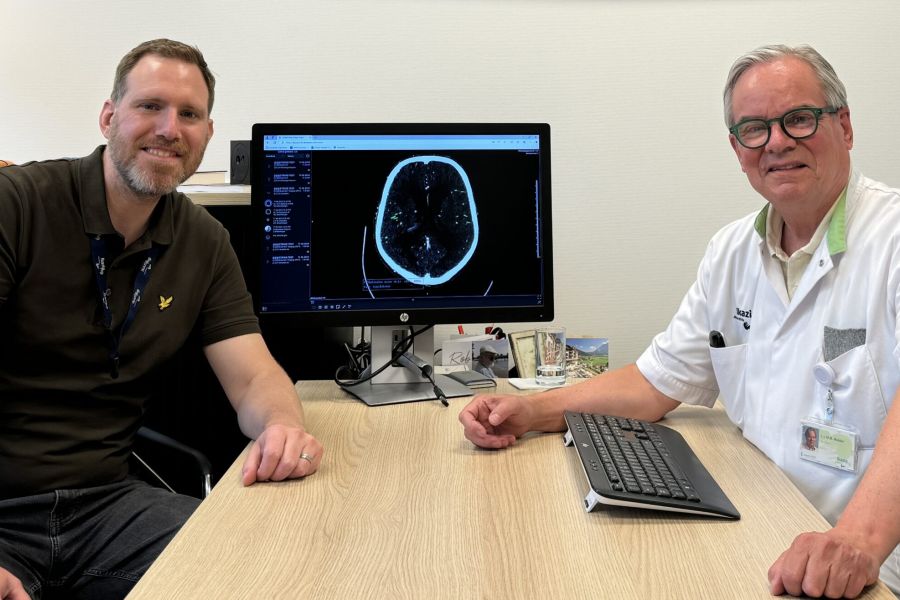

Catharina Ziekenhuis erkend als Topklinisch Expertisecentrum voor herseninfarct op jonge leeftijd

april 21, 2026

Als een jonge vrouw of man een herseninfarct krijgt, staat het leven ineens stil. Juist voor deze patiënten heeft het Catharina Ziekenhuis nu een STZ-erkenning als Topklinisch Expertisecentrum voor Young Stroke gekregen. Een herseninfarct wordt vaak gezien als iets dat vooral oudere mensen overkomt. Toch krijgen ook jongere volwassenen ermee te maken. En voor hen zijn de […]

Veel jonge mensen houden cognitieve klachten na een herseninfarct

januari 14, 2026

Denkproblemen blijven vaak bestaan en beïnvloeden het werkzame leven Cognitieve problemen komen vaak voor bij jonge mensen die een herseninfarct hebben gehad. Deze klachten houden bij een groot deel van hen langdurig aan. Het gaat onder meer om een tragere informatieverwerking, taalproblemen en geheugenstoornissen. Bij ernstige cognitieve klachten neemt bovendien het risico op werkloosheid toe. […]